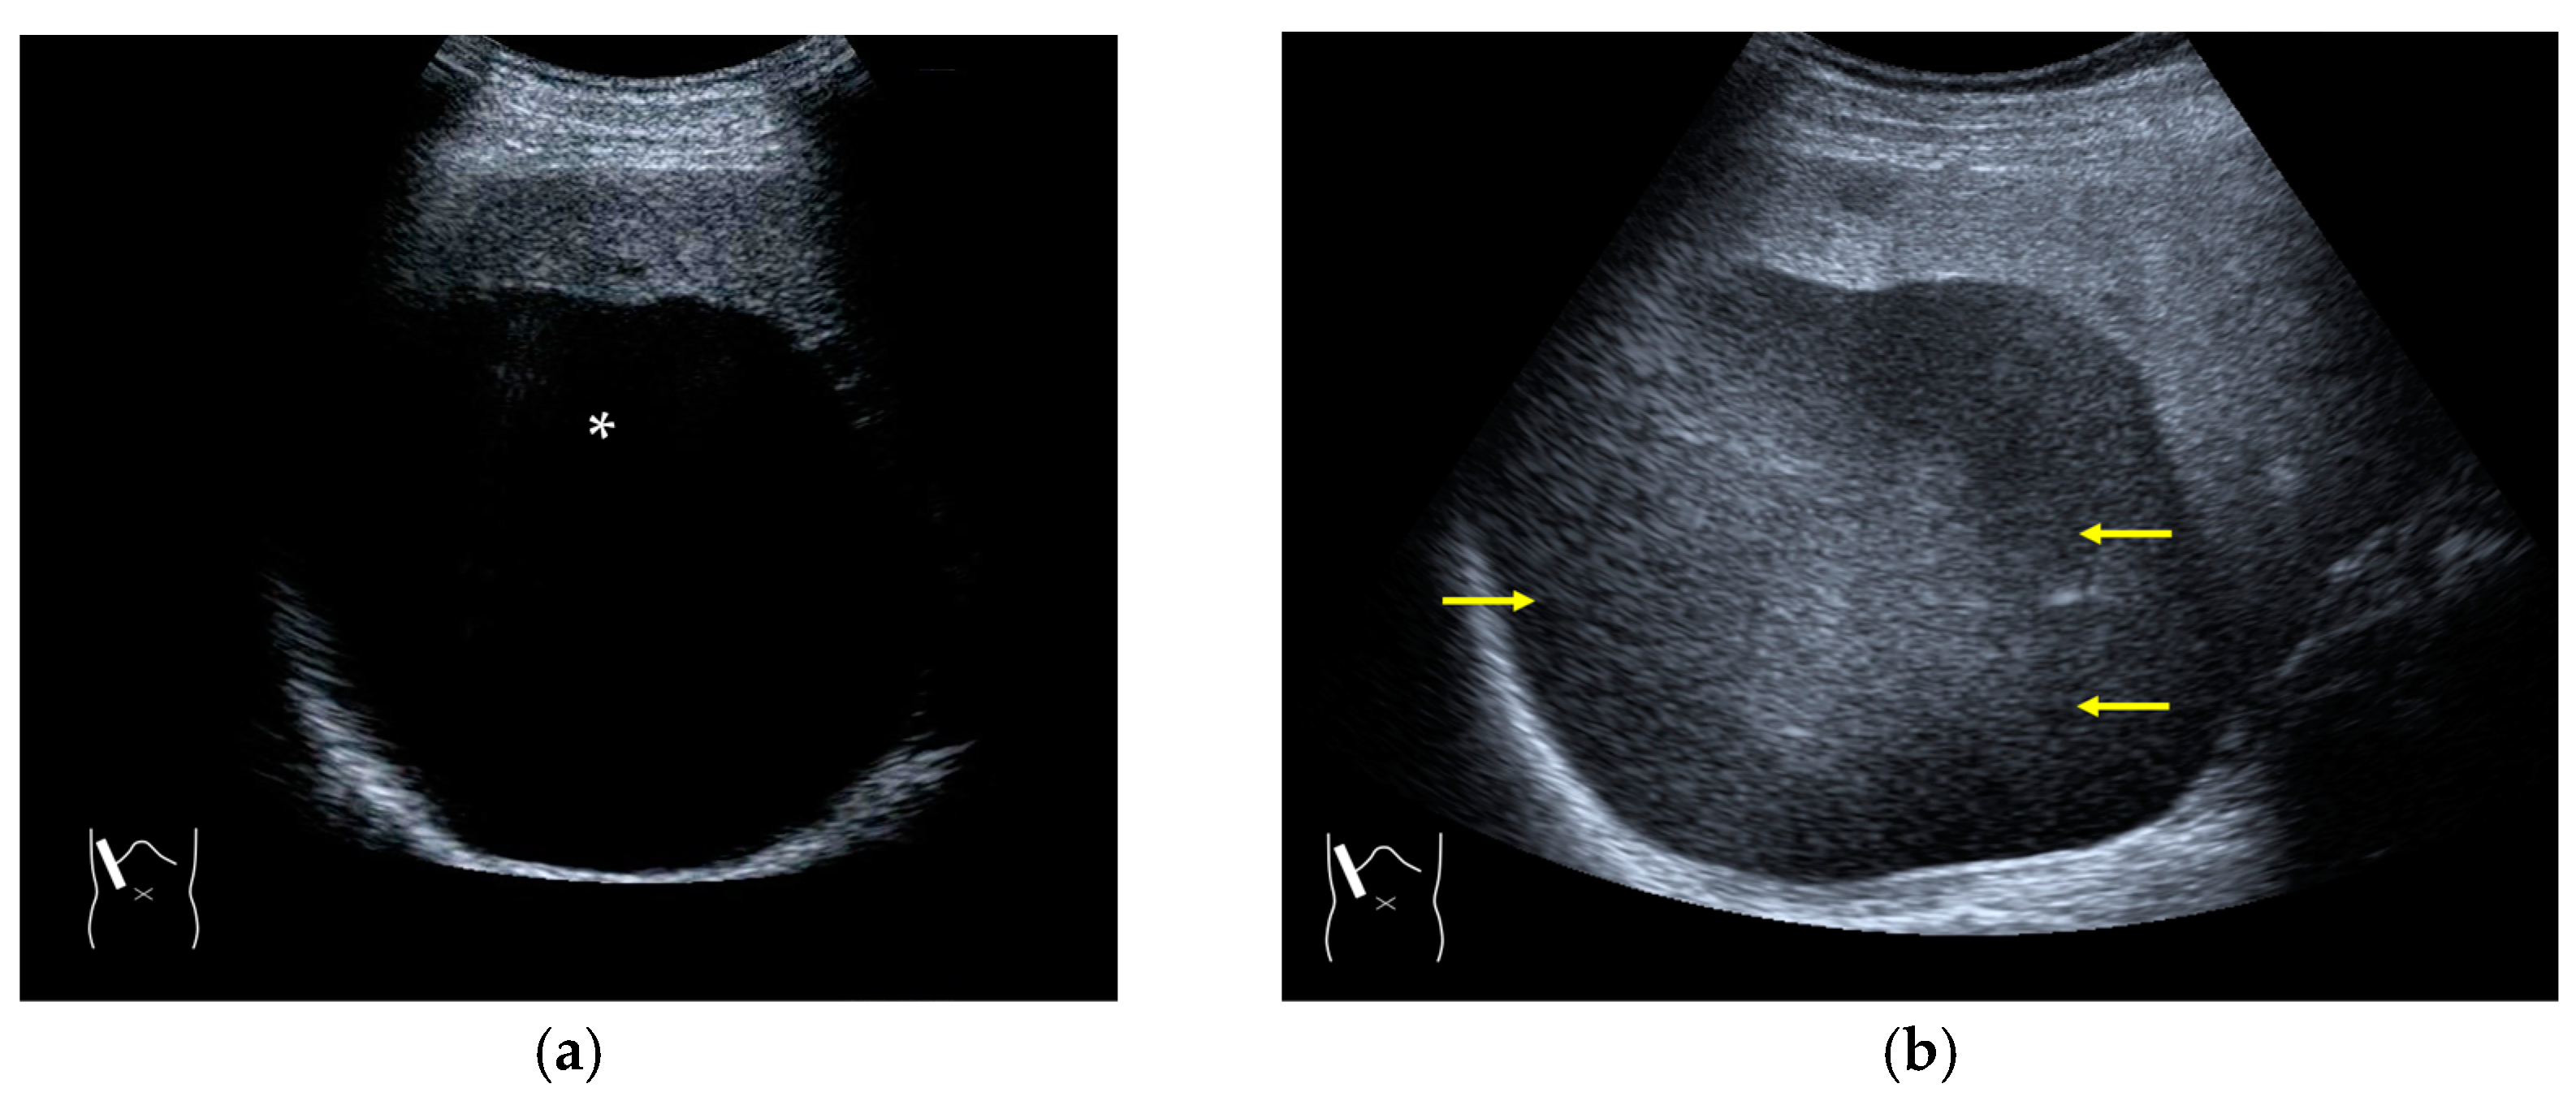

Figure 3.

Refraction artifact (1): many vertical bands of different echogenecities in macronodular cirrhosis. (a) Gray-scale US reveals that the left hepatic lobe is markedly deformed with an irregular surface. The liver gives the appearance of a tricolor flag. (b) CEUS shows the liver to be composed of many vertical bands of different brightness (arrows), giving the appearance of a tricolor flag.

Figure 4.

Refraction artifact (2): heterogeneous enhancement behind a mass lesion (liver metastasis). (a) Gray-scale US shows a 5 × 4 cm liver mass (arrows) in the right lobe. (b) CEUS shows it to be enhanced (black arrows, mass lesion). The liver parenchyma behind it is also coarsely enhanced (arrowheads). (c) A schematic drawing of sound refraction through a round mass (black circle) shows that the US beam is refracted twice at the liver parenchyma–mass lesion interface. Non-refractive lines are marked with solid and dashed pink lines. When the acoustic velocity in the mass is less than that in surrounding tissue, it is indicated with an orange line. When it is greater than that in surrounding tissue, it is indicated with a green line.